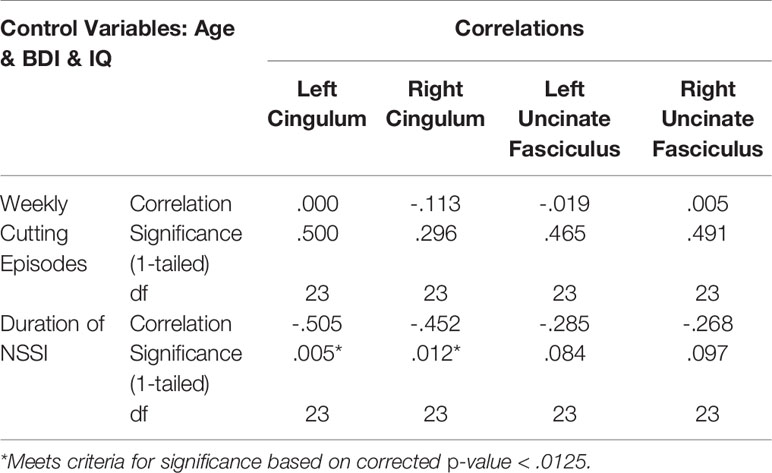

We also explored whether there were any associations between NSSI severity (frequency and duration of NSSI) and GFA in the cingulum and uncinate fasciculus. We used a one-tailed p-value < .0125 in recognition of 4 comparisons for each NSSI frequency and duration.

Lower GFA of the left and right uncinate fasciculus was associated with higher total scores on the attentional subscale of the BIS. A correlation matrix can be found in Table 2, which includes comparisons that were significant at an uncorrected p < .05. For the left and right cingulum, there were no significant associations with measures of self-regulation (DERS and BIS). A correlation matrix can be found in Table 3. Finally, lower GFA of the left cingulum was associated with a longer duration of NSSI. There were no significant correlations between other severity indices (e.g., average number of episodes) and GFA. These in addition to results from other comparisons can be found in the correlation matrix in Table 4.

We also found that longer duration of NSSI was associated with lower GFA within the left and right cingulum. Because we controlled for current age in these analyses, this finding suggests that the impaired white matter integrity of this region among those with NSSI may be the result of a cumulative effect over time. However, it is also important to consider the high likelihood that any existing psychopathology had developed concurrently, or had already existed, around the time of first NSSI episode. Although some studies have reported null findings regarding differences in FA of the cingulum between psychiatric samples and controls (48, 49), a meta-analysis of adolescents with major depressive disorder (MDD) found that overall, those with depression had decreased FA within this region (50). Our finding highlights the importance of early intervention and the utility it may have in preventing aberrant, or restoring normal, neurodevelopmental trajectories. Further, given the number of functions in which the cingulum plays a role, including emotion processing, pain, and executive functioning (18), it is imperative that there is continued investigation into this possible disruption as it may lead to entrenchment of maladaptive behaviors and poorer prognosis.

The cross-sectional design of this study is also a limitation, particularly when interpreting the association between longer duration of NSSI and lower GFA. While we do believe this finding supports a treatment approach with an earlier intervention and prevention, it is still imperative to fully explore whether this white matter disruption was present before or after NSSI onset. Longitudinal designs may also help in developing our understanding of the mechanisms of change with successful intervention strategies, which may then be used to target neurobiologically-based deficits associated with NSSI.